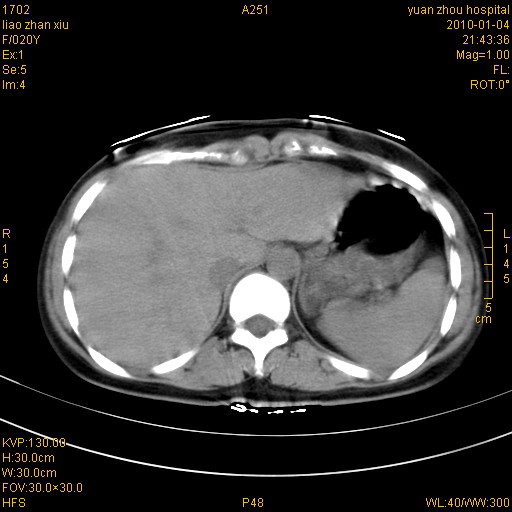

标题: CT23985:F20Y 外伤典型病例 [打印本页]

标题: CT23985:F20Y 外伤典型病例

左肾挫伤,包膜下积血。

左肾挫裂伤伴肾被膜下积血!另:肾周筋膜增厚!

1)左肾包膜下血肿。2)左侧肾挫伤可能;建议:行ct增强扫描检查。3)腰椎左侧横突骨折。

左肾挫伤,包膜下积血,l3、4左侧横突多发骨折。

双侧肾胞膜下出血,左侧较多。l3、4左侧横突多发骨折。

1、左肾挫伤,包膜下积血;

2、l3、4左侧横突多发骨折;

3、腹腔积气,考虑肠管破裂?

左肾挫伤,包膜下积血,L1、2、3、4左侧横突多发骨折。